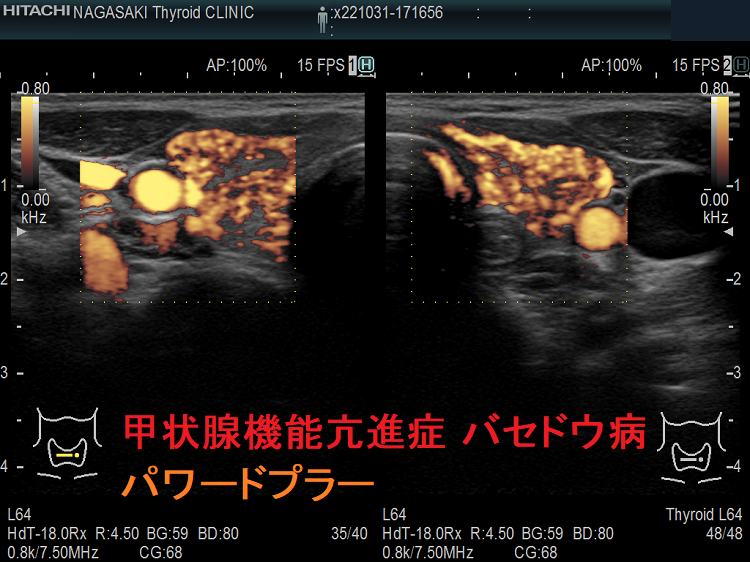

甲状腺機能亢進症・バセドウ病

甲状腺機能亢進症・バセドウ病 通常ドプラー

甲状腺機能亢進症・バセドウ病 通常ドプラーモード

甲状腺機能亢進症・バセドウ病 パワードプラー

甲状腺機能亢進症・バセドウ病 パワードプラー;通常ドプラーモードよりも感度が高いです。

甲状腺機能亢進症バセドウ病 火炎状血流増加

甲状腺機能亢進症/バセドウ病の火炎状血流増加;著明な血管増殖のため甲状腺内の血流が増加します。

しかし、無痛性甲状腺炎でも、甲状腺機能低下症でも血流増加するため、これだけでは鑑別できません。

甲状腺機能亢進症 バセドウ病 火炎状血流増加

甲状腺機能亢進症/バセドウ病の火炎状血流増加